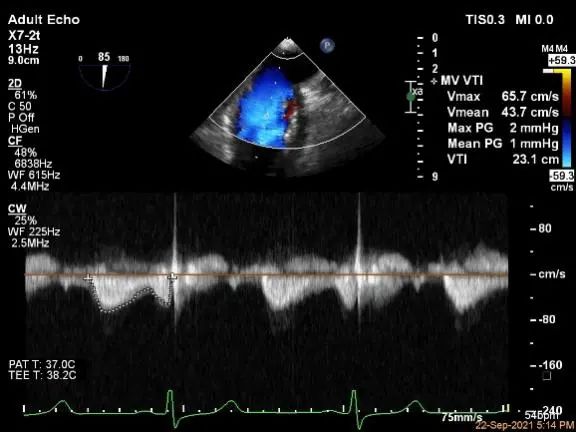

麻醉状态下肺静脉血流频谱

MVA:7.8cm2,平均跨瓣压差:1mmHg

评估二尖瓣瓣口平均跨瓣压差:1mmHg

肺静脉血流频谱恢复正常